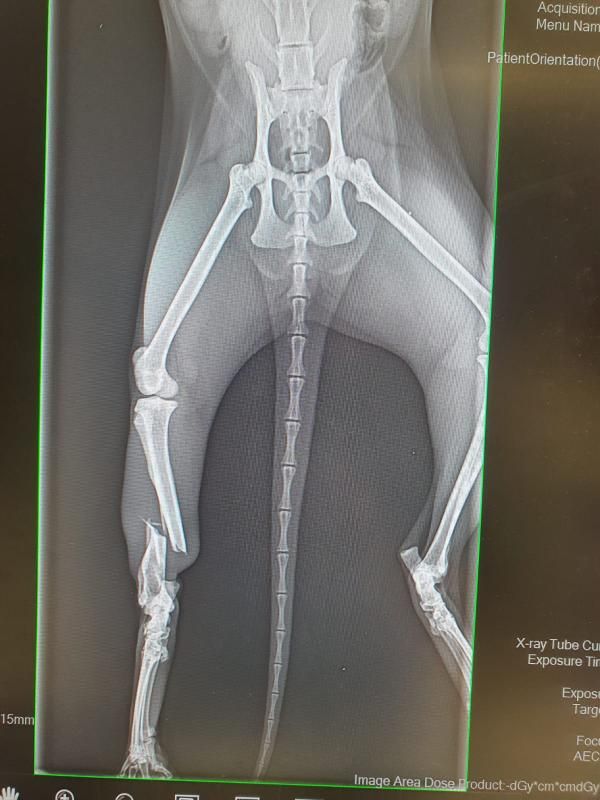

Nymera kam über die Polizei zu uns. Sie wurde von ihrem Besitzer einige Zeit weggesperrt und unversorgt zurückgelassen. Zu allem Übel haben wir festgestellt, dass das rechte Hinterbein gebrochen ist. Am 30.10.2025 haben wir einen Kliniktermin und hoffen sehr, dass sein Bein gerettet werden kann. Also heißt es "Daumen drücken"!